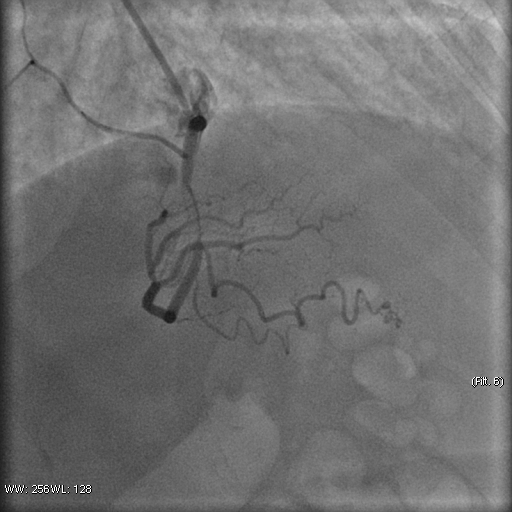

Stenosis of the anterior interventricular artery in the 6.7 segment is 95%. Stenosis of the orifice of the diagonal artery of the 1st order is 95%. Stenosis of the circumflex artery in the 13th segment is 40%. During coronary angiography, pronounced spasm is noted in the 2nd segment of the right coronary artery with complete occlusion of the artery lumen. After stopping the spasm, coronary angiography shows a spiral (spontaneous) dissection of the right coronary artery from segments 1 to 3.

A guiding catheter JR 3.5 6Fr was inserted along a 0.035" 260.0 cm guidewire. The guidewire was removed. The right coronary artery was catheterized. A 7Fr Y-click connector (complete with an insertion device and a guidewire rotation device) was connected to the guiding catheter. A coronary guidewire Whisper ES 0.014" 190 cm, Asahi Gaia Third 0.014" 190 cm was inserted and brought into the orifice of the right coronary artery. The guidewire was inserted beyond the lesion zone of the right coronary artery in segment 2, then into the distal sections. Wilma NC 2.00*20.0 mm and Wilma NC 3.00*15.0 mm balloon catheters were inserted alternately along the coronary guidewire - predilation of the lesion zone of the right coronary artery in segment 2 was performed. Inflation of balloon catheters 14 atm. with an inflator, the balloon catheters are deflated and removed. A stent is inserted along the coronary guidewire - the Yukon Chrom PC 3.0 * 28.0 mm system, Yukon Chrom PC 3.0 * 28.0 mm, Cid Cre 8 3.50 * 25.0 mm, Cid Cre 8 4.0 * 16.0 mm - the stent is implanted in the lesion area of the right coronary artery in the 2nd segment. Inflation of the balloon catheter 9-16 atm. with an inflator, the balloon catheter is deflated and removed. Control coronary angiography - blood flow in the stenting zone is TIMI3, there are no signs of dissection or stent dislocation.